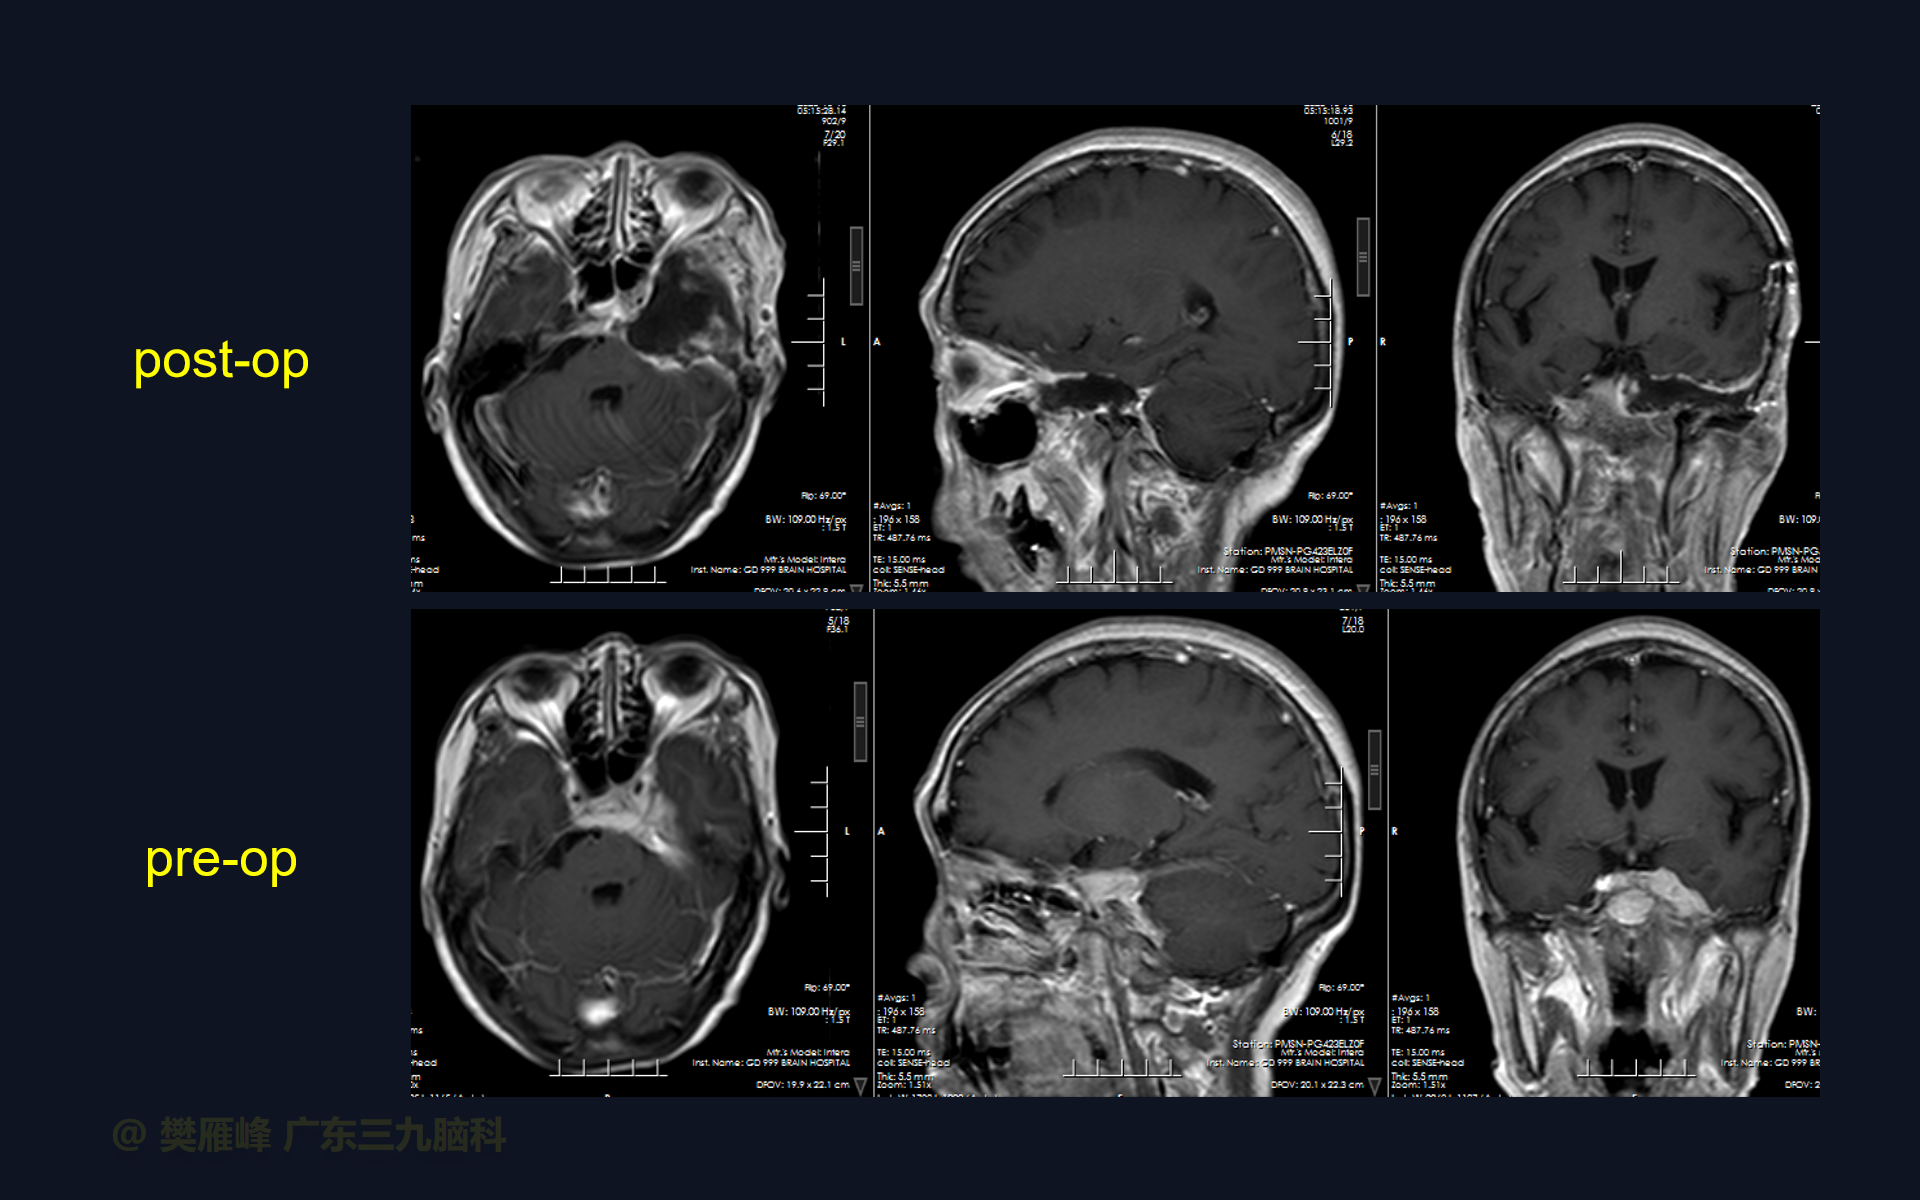

在这个二维手术视频中,展示了一种经扩大的中颅窝底入路硬膜外磨除Kawase三角切除蝶岩斜区复发脑膜瘤的方法。患者是一名55岁的女性,有6年的左耳听力下降行经乙状窦后入路岩斜脑膜瘤切除,术后左侧眼球运动障碍伴左侧面部歪斜、左侧听力下降;1月前复查发现蝶岩斜区脑膜瘤复发,神经影像学显示左侧鞍区、海绵窦、岩斜区团块状占位,累及蝶窦后部并侵进垂体窝,形态不规则,呈等T1等T2、FLAIR高信号为主,明显强化,邻近硬脑膜强化。他接受了经扩大的中颅窝底入路硬膜外磨除Kawase三角切除蝶岩斜区复发脑膜瘤,手术耐受较好,肿瘤大部切除。术后左侧眼睑下垂,左侧面瘫,左耳听力基本丧失等情况同前。神经影像学显示肿瘤大部切除。术后1月后行放疗。我们展示了安全的颅神经和肿瘤切除术的细微差别和技术要点,以及手术技术,以留下最少的残余粘附肿瘤。

在这段手术视频中,展示了一名55岁女性的病例,他因左侧眼球运动障碍伴左侧面部歪斜、左侧听力下降6年复查发现的左侧蝶岩斜区复发脑膜瘤。